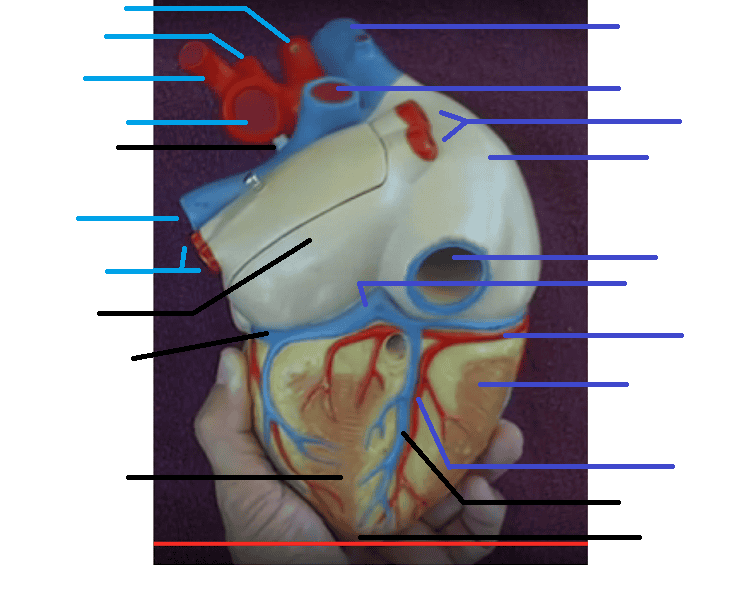

Name the missing parts.

Heart external anterior view

Name the missing parts.

External posterior view

Name the missing parts.

External anterior view

Name the missing parts.

Frontal section